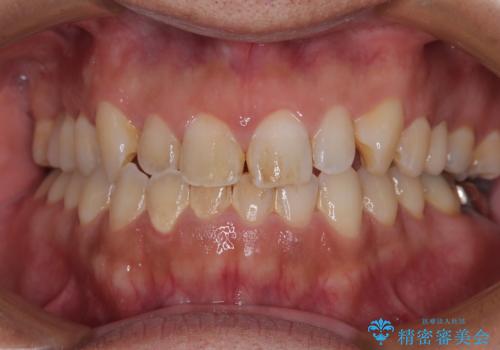

歯根だけとなっている歯はインプラントに、神経組織の失活している歯は根管治療を行い、いずれもオールセラミッククラウンにて補綴治療を行うこととしました。

インプラント処置は、抜歯即時埋入を行い、十分な安定性が確認できたため、当日仮歯を装着しました。

インプラントが生着するのを待っている間に反対側の根管治療を行い、左右同時に補綴治療を行いました。

補綴治療後3ヶ月での経過は良好で、引き続き経過観察を行っていきます。